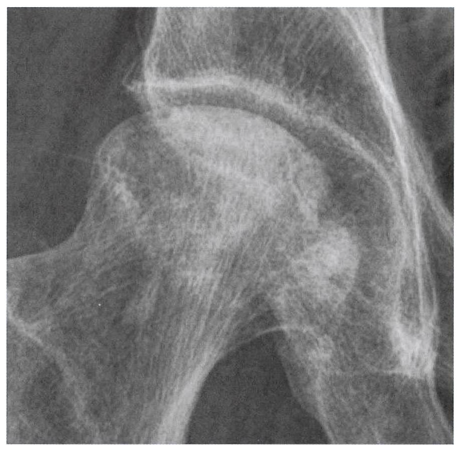

방사선 소견

관절 간격이 좁아지고 연골하 경화, 골극형성 등

퇴행성 관절염의 특징적 소견이 모두 나타납니다.